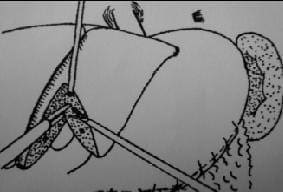

Se inició la disección del ligamento falciforme para delimitar el sitio de la segmentectomía según la demarcación del área isquémica posterior a la ligadura vascular (figura 5). Luego, se disecó el ligamento triangular izquierdo y, por tracción medial del hígado, se liberaron los segmentos II y III en el área ciega hasta encontrar la vena suprahepática izquierda en el borde superior y el lóbulo caudado en el borde inferior (figura 6).

FIGURA 5. Disección del ligamento falciforme y posteriormente del ligamento triangular izquierdo. |

FIGURA 6. Finalización de la liberación del área ciega del hígado y disección de la vena suprahepática izquierda. |